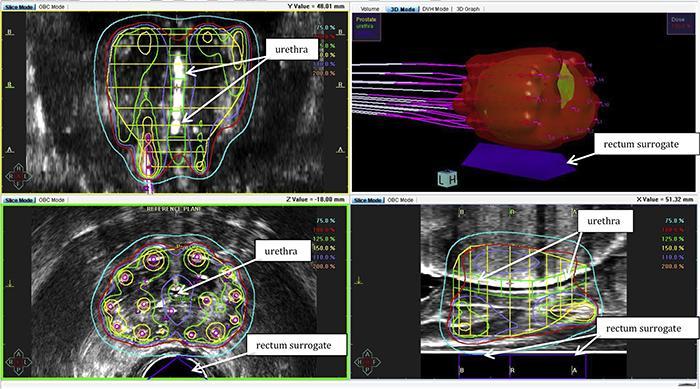

ESTRO President Prof. Yolande Lievens, head of the department of radiation oncology at Ghent University Hospital, Belgium, said, "Advances in radiotherapy mean that we are better able to locate and target tumors while minimizing damage to nearby organs. In prostate cancer, this can mean men retaining urinary and sexual function. This also means that we can consider giving higher individual doses over a shorter time, as in this study.